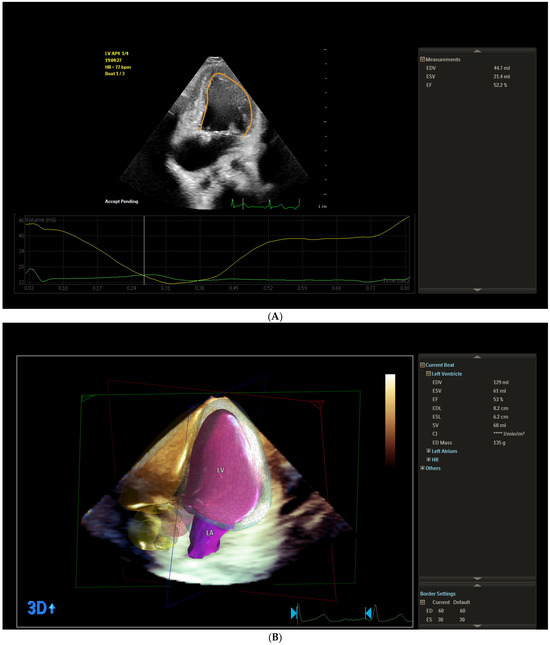

It is our honor to invite you to contribute to this Special Issue of the Journal of Clinical Medicine, entitled “Application of Echocardiography in the Diagnosis and Management of Cardiac Diseases”. Transthoracic echocardiography is the most effective, low-cost, minimally invasive, and readily available imaging modality for the assessment of patients exhibiting cardiac symptoms. It plays a central role in identifying or ruling out suspected acute and chronic cardiac diseases. Second, echocardiography is essential in follow-up on previously diagnosed valvular disease or heart failure. In those with heart failure, it would provide meaningful information to better treat the patient. In addition, novel techniques (transesophageal, stress, contrast, myocardial strain imaging, and three-dimensional (3D), intracardiac, echocardiography) have expanded the indications in a variety of ways and a wide range of clinical situations. Bedside echocardiography is routinely used now for patients who are critically ill with known or unknown cardiac diseases in order to elucidate the etiology of cardiovascular and respiratory failures. The role of echocardiography is increasing in patients who are asymptomatic and had, for example, a family history of sudden death, or in athletes. In this Special Issue, we aim to collect original articles and reviews focusing on the role of echocardiography on the whole spectrum of diagnosis and management of cardiac diseases. Multidisciplinary manuscripts are also welcomed.